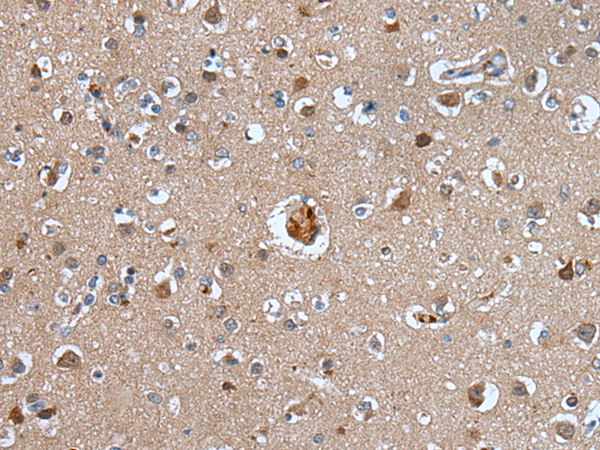

分类: 科研抗体货号: P12907别名:应用: IHC反应种属: Human, Mouse, Rat